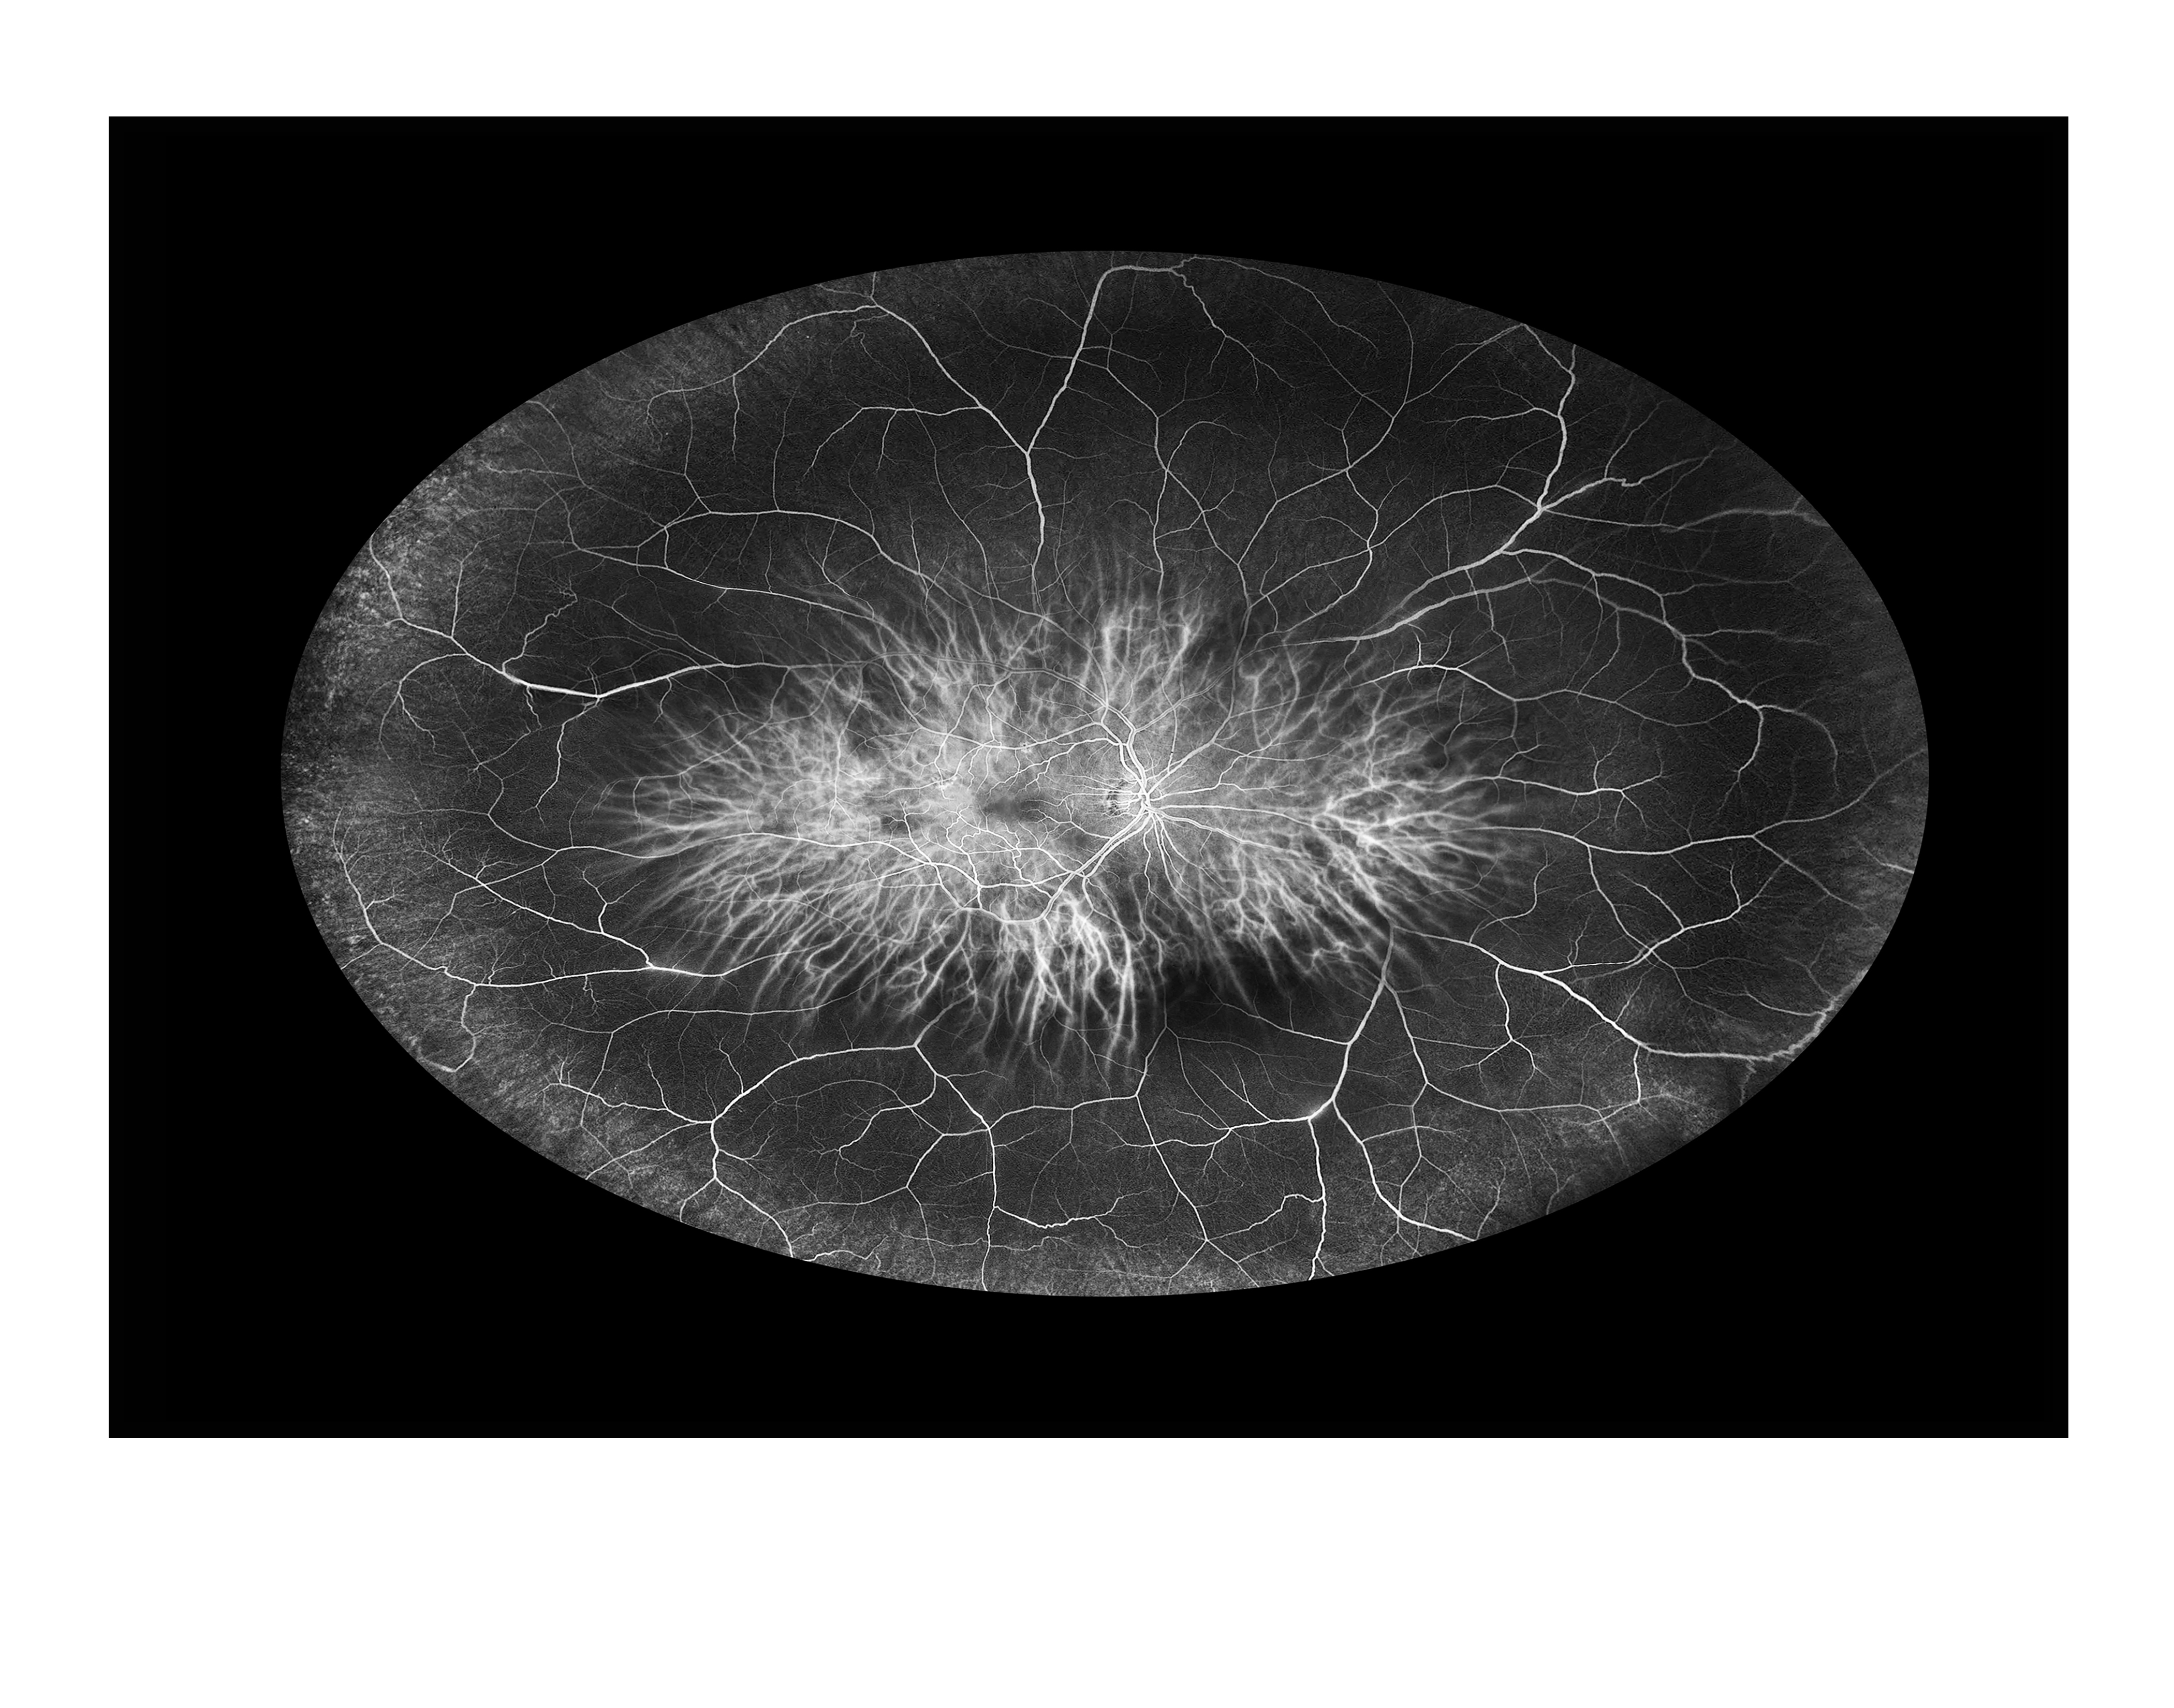

Composite Unknown Presented by Albert Alimpich This photograph received Second Place in the category "Composite" and was displayed in the 2024 OPS Exhibit. Filed Under Retina OPS Photo